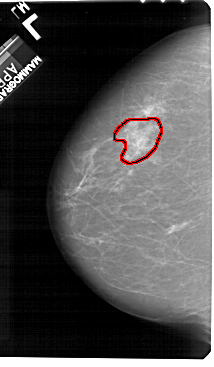

A_1273_1.LEFT_CC

LEFT_CC LINES 5491 PIXELS_PER_LINE 3196 BITS_PER_PIXEL 12 RESOLUTION 43.5 OVERLAY

FILE: A_1273_1.LEFT_MLO.OVERLAY

TOTAL_ABNORMALITIES 1

ABNORMALITY 1

LESION_TYPE CALCIFICATION TYPE PUNCTATE DISTRIBUTION SEGMENTAL

ASSESSMENT 4

SUBTLETY 1

PATHOLOGY BENIGN

TOTAL_OUTLINES 1

BOUNDARY